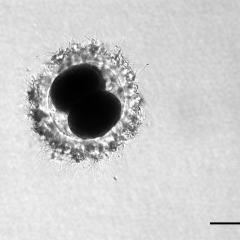

Oocyte Zygote

Zygote Whole Embryo